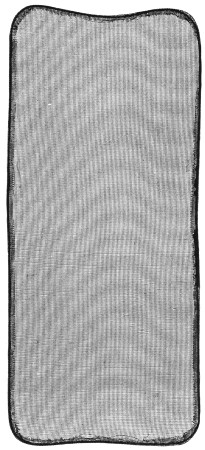

54. Wire Gauze Splint 187

56. Cane Field Splint for Lower Extremity 209

58. Cane Field Splint for Leg 222